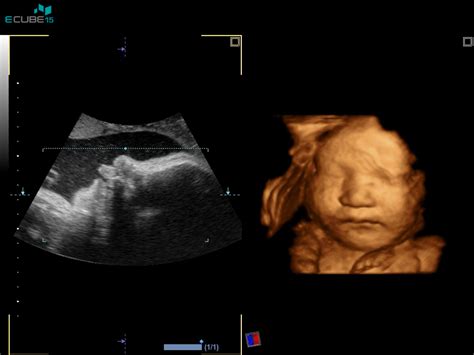

Kajenje med nosečnostjo predstavlja neposredno grožnjo razvoju še nerojenega otroka. Kemične snovi iz tobačnega dima, kot so nikotin, ogljikov monoksid in številni drugi strupi, prehajajo skozi posteljico neposredno v otrokov krvni obtok. Ta izpostavljenost lahko povzroči vrsto negativnih posledic, ki segajo od zmanjšane rasti in nižje porodne teže do resnih prirojenih napak.

Znanstvene študije nedvoumno kažejo na povečano tveganje za prezgodnji porod, prezgodnjo ločitev ali predležečo posteljico, kar lahko ogrozi tako življenje matere kot otroka. Zmanjšana pljučna funkcija pri otroku, ki se rodi materi, ki je kadila med nosečnostjo, lahko vodi do dolgotrajnih težav z dihanjem. Povečana je tudi verjetnost za razvoj prirojenih napak, kot je razcepljena ustnica ali volčje žrelo. Poleg tega obstajajo dokazi, ki povezujejo kajenje matere s spontanim splavom in povečanim tveganjem za sindrom nenadne smrti dojenčka (SIDS), ki je eden najtragičnejših in najbolj nepojasnjenih vzrokov smrti dojenčkov.